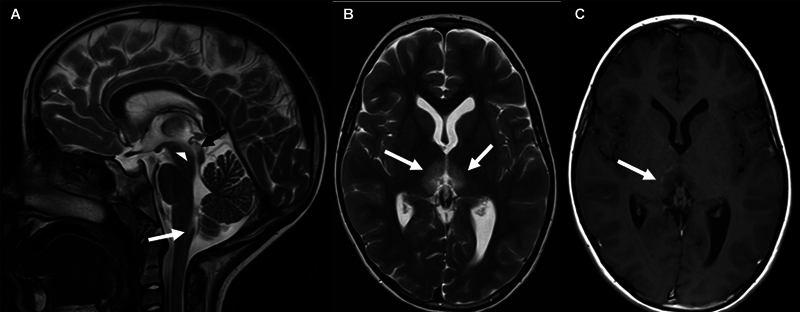

神经脊髓炎视谱障碍(NMOSD)是一种罕见的神经炎症性疾病,在白人人群中年发病率少于1例,发病年龄中位数为40岁。NMOSD通常表现为视神经炎和纵向广泛的横断面脊髓炎。各种脑干、小脑、间脑和半球症状也可能发生。早期诊断和治疗对于症状管理和预防复发和残疾至关重要。我们报告的情况下,青春期前的女孩,突出独特的临床和MRI特征和早期实质损害的风险。

Neuromyelitis optica spectrum disorder (NMOSD) is a rare neuroinflammatory disease with an annual incidence of less than 1 case in 1,000,000 in the White population and a median age of onset at 40 years. NMOSD usually presents with optic neuritis and longitudinally extensive transverse myelitis. Various brainstem, cerebellar, diencephalic, and hemispheric symptoms may also occur. Early diagnosis and treatment are crucial for symptom management and prevention of relapses and disability. We report the case of a prepubertal girl, highlighting unique clinical and magnetic resonance imaging features and the risk of early parenchymal damage.